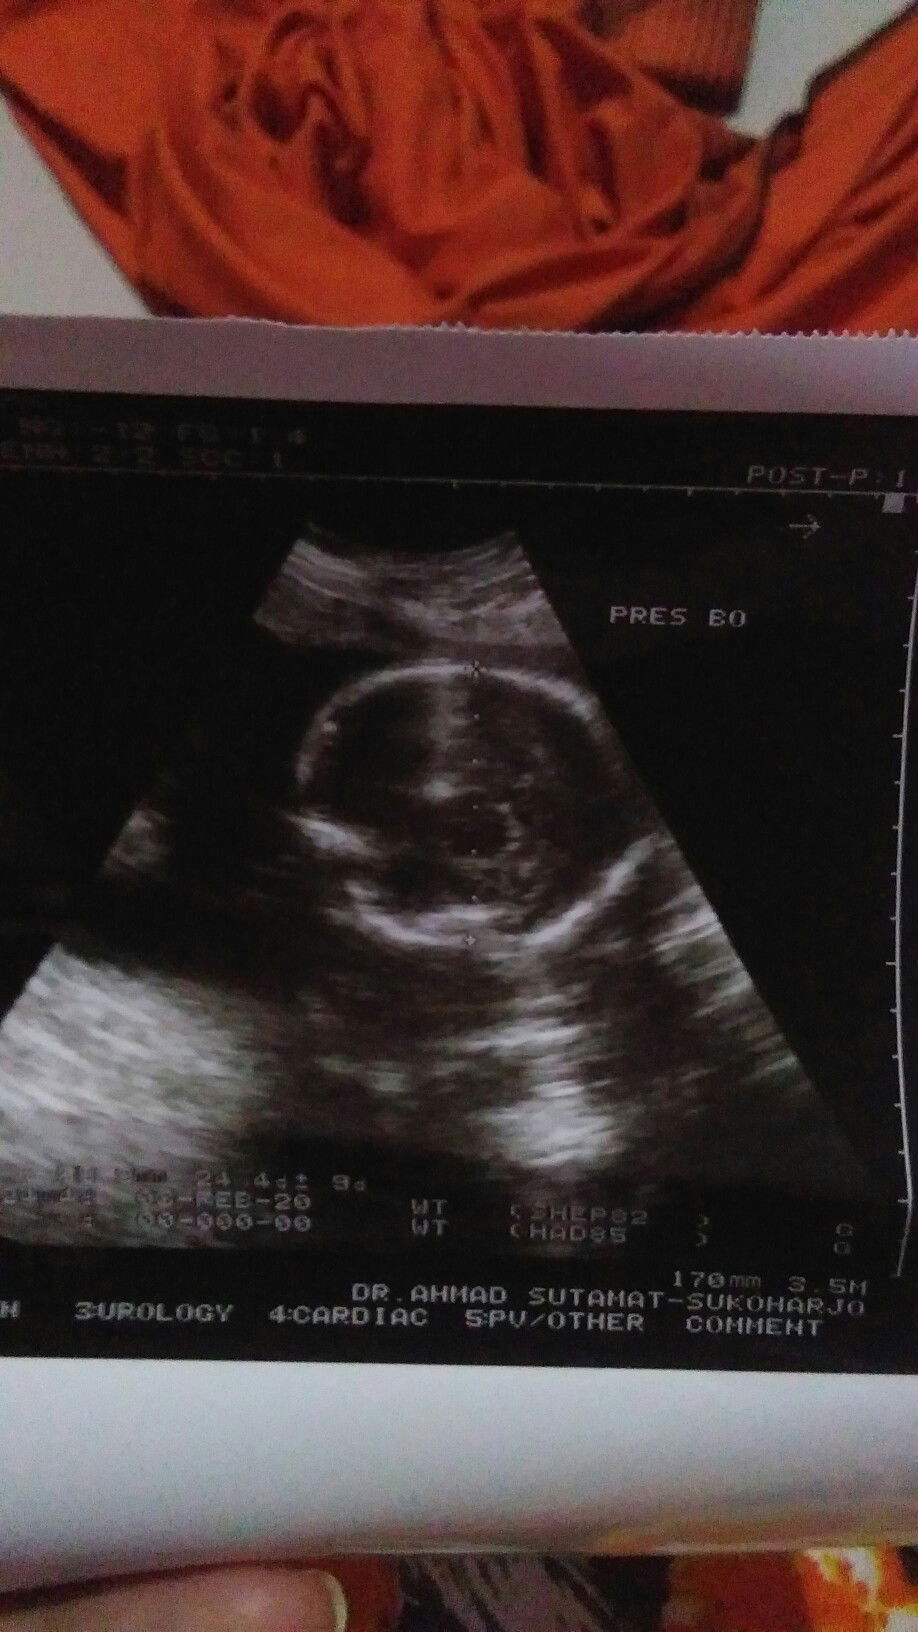

Ramadan tahun lalu Sanjay berkesan dengan berkumpul bersama keluarga, bisa beribadah bersama Sama, berbuka Pulsa bersama, Tahu gak TAP ramadan tahun lalu begitu berkesan karna saya akan di karunia anak yang ke2 karna gak ketahuan mau hamil sampai2 saya bisa puasa full sebulan tapi akibatnya, sehabis lebaran saya pun harus di rawat di rumah sakit bedrest karna mengalami pendarahan.. Dan alhamdulillah nya, baby dalam kandungan masih rezeki saya dan sekarang sudah berada di tenggah2 keluarga besar kami... Banyak sekali perjuangan saya dan baby dari mau ada sampai lahiran banyak drama tercipta... Syukur alhamdulillah semua terlewati dengan baik... Sehat selalu anak mama...... #ramadanbersamaTAP